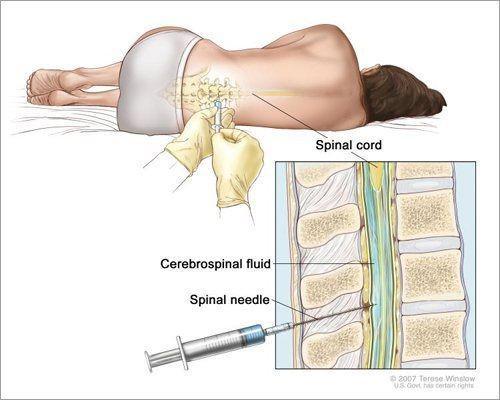

Sebelum tes, ahli radiologi akan menyuntikkan media kontras (juga disebut bahan kontras atau pewarna) ke dalam kanal tulang belakang melalui punggung bawah. Kemudian, ahli radiologi mungkin mengambil beberapa rontgen tulang belakang (informasi lebih rinci bisa didapat melalui pemindaian CT tulang belakang setelah injeksi). Pewarna akan menyatu dengan cairan tulang belakang, memberi ahli bedah atau ahli saraf pandangan yang jelas pada tulang dan jaringan lunak yang mungkin menyebabkan gejala.

Merangkum Spine-health.com, myelography biasanya melibatkan penyuntikan pewarna kontras ke dalam ruang subarachnoid kanal tulang belakang, yang mengelilingi sumsum tulang belakang dan akar saraf.

- Kamu akan berbaring tengkurap di atas meja sinar-X.

- Penyedia layanan kesehatan akan membersihkan punggung kamu dengan larutan antiseptik.

- Kamu akan disuntik dengan obat mati rasa, sehingga tidak akan merasakan sakit selama prosedur.

- Setelah area tersebut mati rasa, penyedia layanan kesehatan akan menggunakan jarum tipis untuk menyuntikkan pewarna kontras ke dalam kanal tulang belakang. Kamu mungkin merasakan tekanan saat jarum masuk, tetapi seharusnya tidak sakit.

- Sampel cairan tulang belakang (cairan serebrospinal) diambil untuk pengujian.

- Penyedia layanan kesehatan akan melepas jarum.